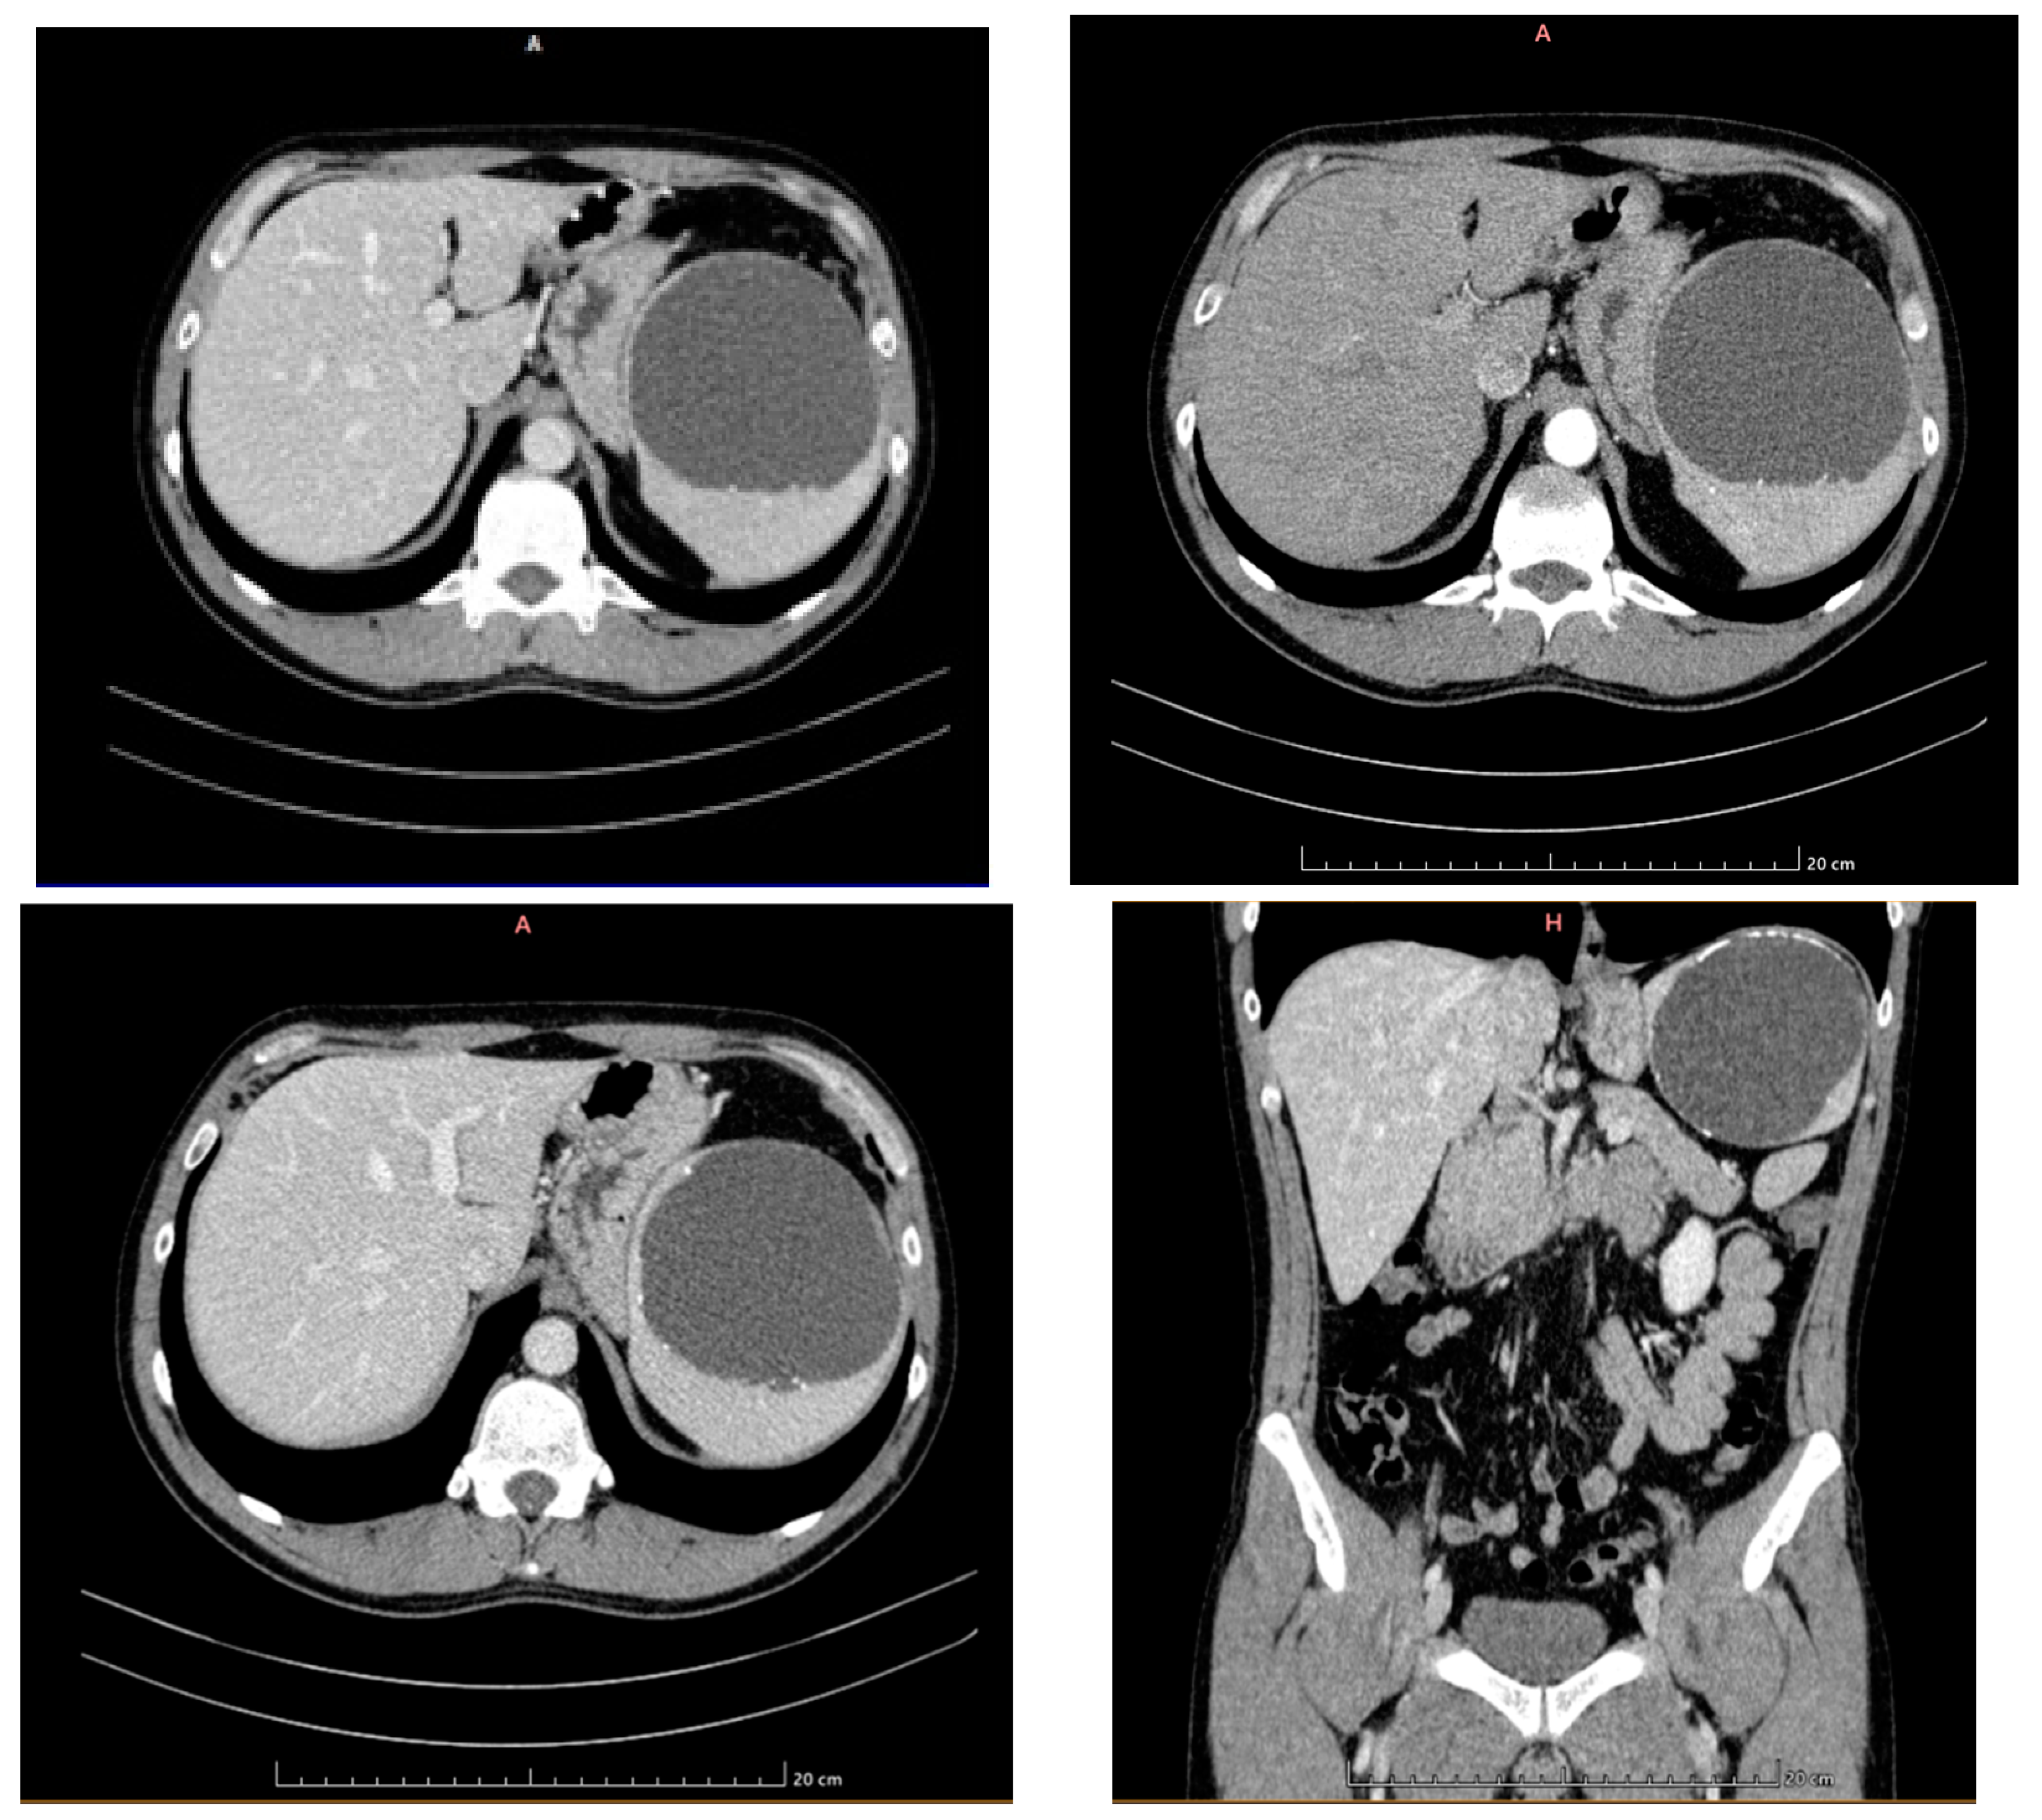

- Capillary hemangioma hepatic segment VII of 8 mm diameter.

- Grade I splenomegaly with simple voluminous splenic cyst, 10 cm in diameter.

- Accessory spleen adjacent to the lower pole of the spleen.